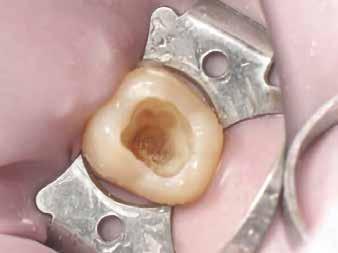

Kiindulópont: egyszerű I. osztályú rágófelszíni kavitás (3. ábra).

Általános szabály, hogy az okkluzális iránytűt csücsökről csücsökre haladva kell felépíteni, mindig a legnagyobb csücsökkel ellentétes oldalon kezdve. Mivel a felső első moláris legnagyobb csücske a mesio-palatinális, a szerző a mesio-bukkális csücskön kezdi a munkát.

A mesio-bukkális háromszöget és a marginális gerincet az adott VITA árnyalatnak megfelelő, alacsony opacitású kompozitból alakítja ki. Ezzel egyidejűleg kialakul a középső bukkális barázda (kék - laterotruzív irány) és a másodlagos mesio-bukkális anatómia (sárga - lateroprotruzív irány).

Az első réteget a „Pulse-Activation” protokoll [13] szerint kell polimerizálni gél-állapotig; ennek kettős előnye, hogy idő takarítható meg vele, másrészt csökkenti a polimerizációs zsugorodási feszültséget a restaurációban (4. a és 4. b ábra). Ezt követően a disto-bukkális háromszög és marginális gerinc kialakítása történik hasonló módon; ezzel befejeződik a középső bukkális barázda kialakítása (kék - laterotrusív mozgás), és létrejön a disto-bukkális csücsök másodlagos anatómiája (piros - lateroresurtrusív mozgás).

Megjegyzésként elmondható, hogy a középső bukkális barázda helyes pozíciója kulcsfontosságú mind a laterotrusív mozgás szempontjából, mind az okkluzális iránytű középpontjának végső helyzetének meghatározásában.

A szerző tapasztalata szerint jól használható támpont, ha gondolatban egy egyenest húzunk a mesio-bukkális csücsök csúcsa és a disto-bukkális csücsök csúcsa között, majd ezt merőlegesen elfelezzük – ez a vonal legtöbbször jól megfelel a középső bukkális barázda helyzetének (5. a és 5. b ábra)

A következő lépés a mesio-palatinális háromszög és marginális gerinc felépítése, egy kisebb bemélyedés megformázásával, amely lehetővé teszi a mediotrusiót (zöld), valamint kialakítandó az ún. Stuart-barázda is. Ezen felül a szerző egy apró, ujj-szerű kiemelkedést is megformáz a mesiális marginális gerinctől az okklúziós iránytűpont felé, amely a fekete jelölésű protrusív mozgást biztosítja (6. a és 6. b ábra).

A felépítés a disto-palatinális csücsök háromszög és marginális gerinc kialakításával fejeződik be. Fontos megjegyezni, hogy a palatinális barázda distális irányba fut, emiatt a mesio-palatinális csücsök nagyobb, mint a disto-palatinális – ez okozza az egyik leggyakoribb hibát az első moláris felépítésekor. Ezen felül pedig egy további iránytűpont vetül mesialis irányba a második moláris mesiális marginális gerincétől; ügyelni kell arra, hogy a disto-palatinális csücsök lejtői ne akadályozzák ennek a mozgásnak a mediotrusív pályáját (7. a és 7. b ábra).